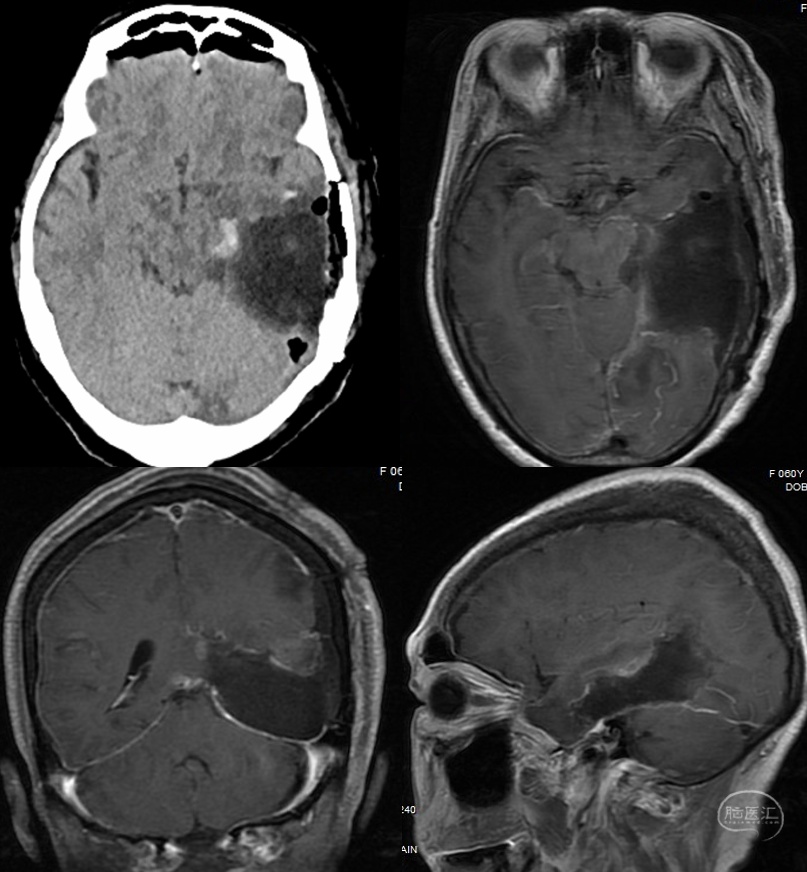

(一)左颞内侧巨大胶质母细胞瘤全切一例

患者,女,60岁,1年前出现记忆障碍伴反应迟钝,症状进行性加重,5个月前突发意识不清伴四肢抽搐1次,5天前出现头痛。

术前检查提示左颞内侧巨大占位,病灶不均匀强化,弥散明显受限。

术后CT、MRI检查提示肿瘤全切,术区出血水肿均不明显。

术后病理提示胶质母细胞瘤,IDH野生型,MGMT非甲基化,预后相对较差。

患者术后接受了同步放化疗联合电场治疗,术后11月复查术区未见复发,侧脑室旁见一小结节,考虑脑脊液播散可能,电场+替莫唑胺治疗中,目前生活可完全自理。